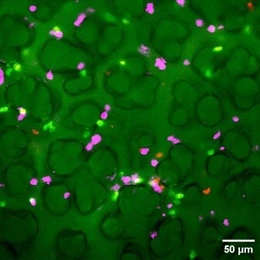

Many environmentally triggered lung diseases are still considered incurable. We explore the immunological mechanisms underlying chronic lung diseases such as COPD, lung fibrosis, asthma, lung cancer and the complications following lung transplantation. We want to translate our findings into preventative and therapeutic approaches for patients.

Many environmentally triggered lung diseases are still considered incurable. We at the Institute of Lung Health and Immunity (LHI) explore the immunological mechanisms underlying chronic lung diseases such as COPD, lung fibrosis, asthma, lung cancer and the complications following lung transplantation. We want to translate our findings into preventative and therapeutic approaches for patients.